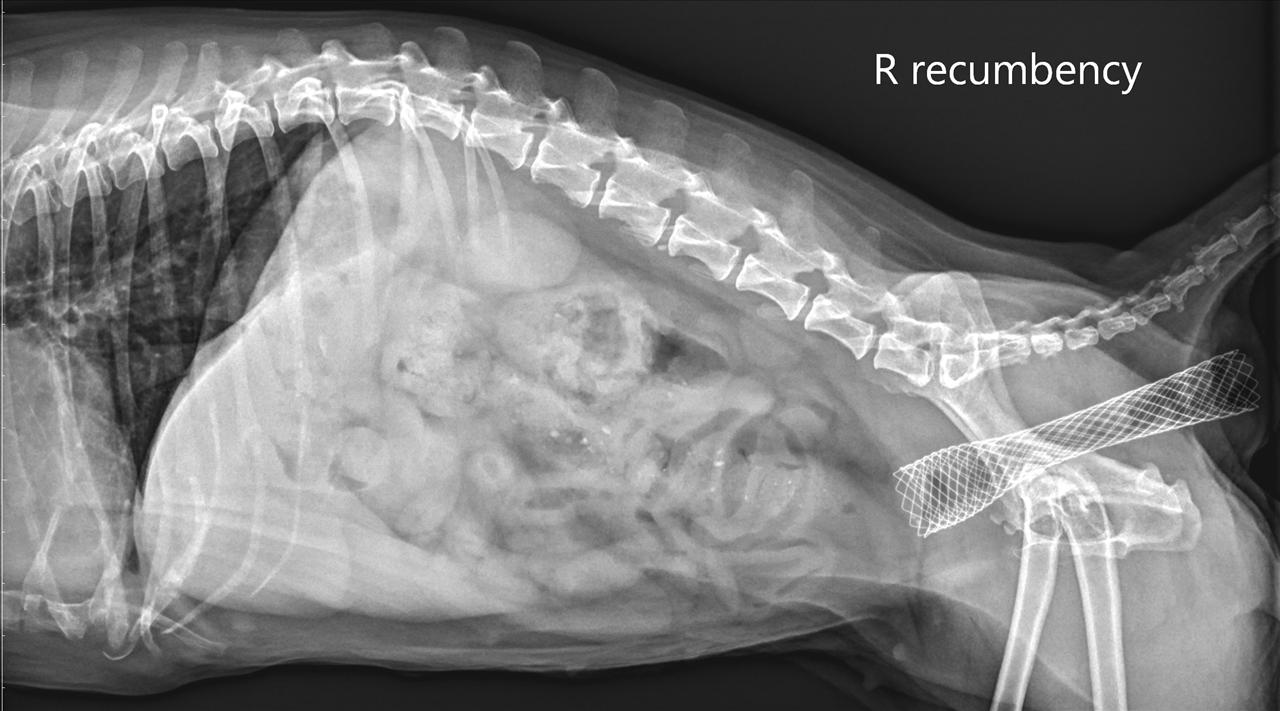

這次手術是將腸道支架由肛門置入,在連續X光透視下,導引支架在腸腔內自動展開,提供一個持續性360度的張力,能有效撐開狹窄區,恢復腸道的通暢。由於是無創的手術,病患不須接受深度的麻醉,且操作時間很短,包含內視鏡檢查大約只需要30分鐘,因此也可大幅減少麻醉時間,對於末期腸癌的病患來說身體負擔較小。

蘇筱晶指出,動物大腸常見的腺癌好發於降結腸及直腸交界處,這個區域的外科手術較不易進行,常需要鋸開骨盆才能夠完整暴露出病灶區,對於體力差的末期病患風險相對提升。若病患經評估無法接受腸切除及吻合術,此時無創放入腸道支架是另一種安寧治療的選擇。